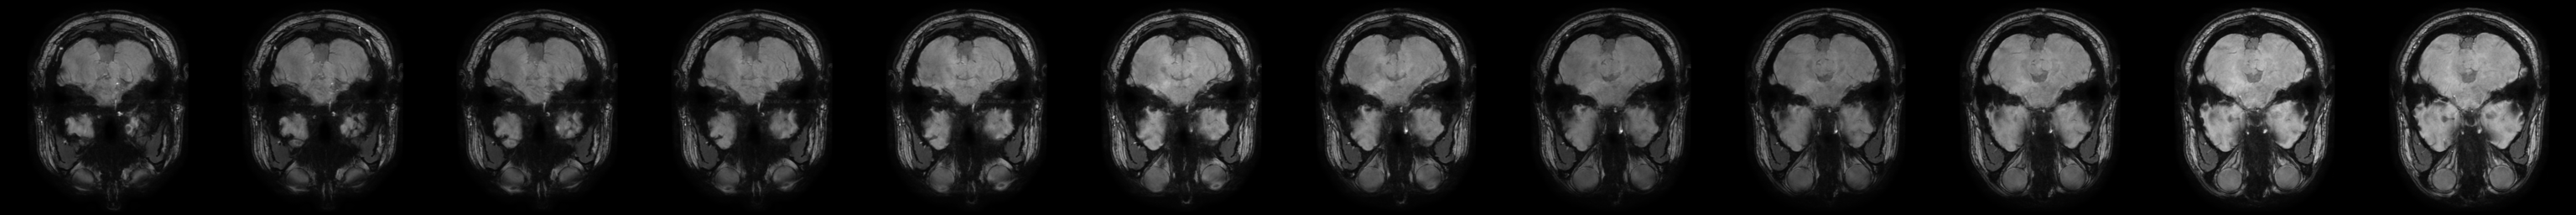

Now we have to combine these images to create our sprites so that the brainspriteR

can visualise them.

sideBySide[[3]]

In the end this is what the sprites look like. We can use this to create our visualisation. You can view different parts of the brain by clicking the area of interest in any of the slices.